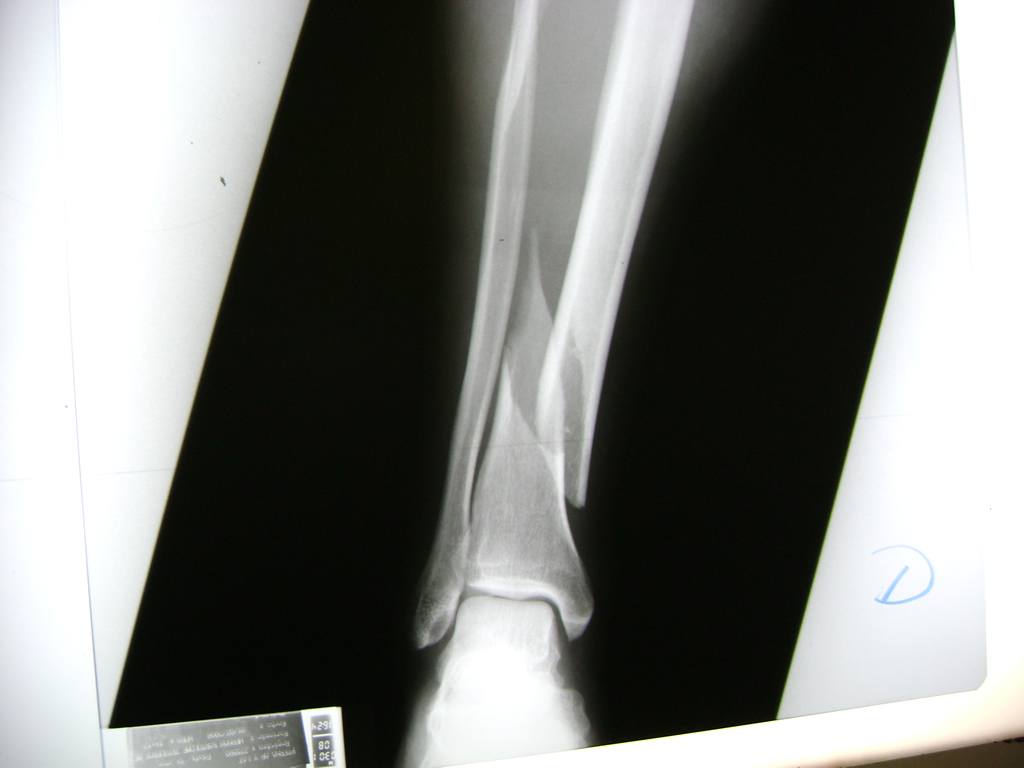

Cirugias en El Salvador - Perone y Tibia

Aunque cada uno de estos huesos puede fracturarse por separado, normalmente la rotura es una lesión que se produce de forma conjunta

La mayor parte de las roturas implican a la parte proximal del hueso (parte del hueso próximo a la rodilla) o a la parte distal (parte del hueso cerca del tobillo).

Debido a la fina cobertura de piel que recubre la tibia y el peroné, las fracturas generalmente son abiertas, es decir, el hueso roto rasga la piel, atravesándola. Las fracturas de tibia y peroné generalmente se producen por un fuerte impacto o torsión.